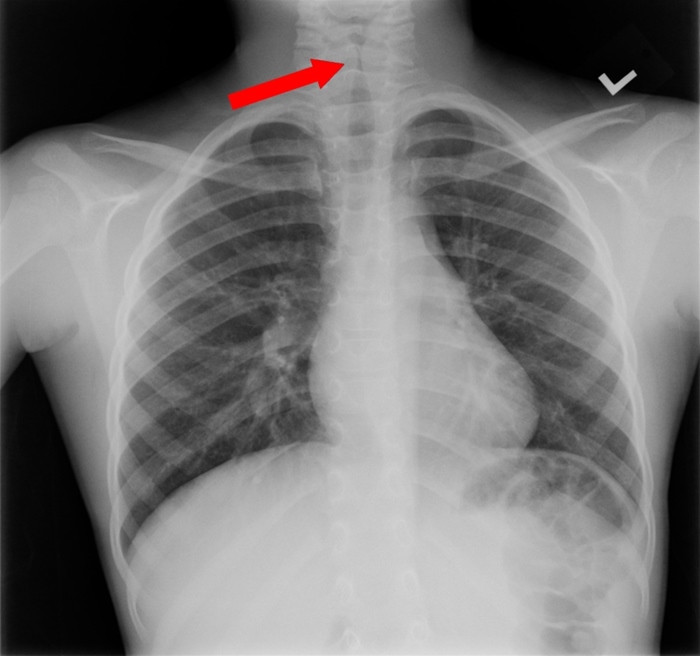

Croup

Croup, or laryngotracheitis, is a viral respiratory illness most commonly caused by parainfluenza virus and typically presents in children age 3-36 months. The illness usually begins with nonspecific symptoms (eg, rhinorrhea, congestion, fever); classic croup then presents with a dry, "barky," seal-like cough, hoarseness, and inspiratory stridor due to upper airway obstruction. The stridor worsens with agitation or excitement and may be inspiratory or biphasic (inspiratory and expiratory) in very severe cases.

Croup is typically a clinical diagnosis. If the diagnosis is unclear, anteroposterior neck radiographs will reveal subglottic edema known as the "steeple sign" (red arrow). Treatment is aimed at reducing subglottic edema; corticosteroids (eg, dexamethasone) are useful for mild cases and nebulized racemic epinephrine is added for patients with stridor at rest.